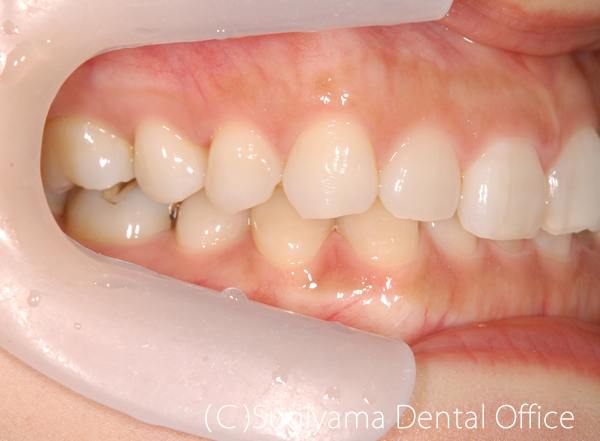

術前症例写真

術後症例写真

前歯を綺麗にしてほしいということで来院した女性の患者さんです。

親知らずは抜歯しましたが、そのほかは1本も歯を抜かずに矯正治療を仕上げました。

変色が著しかった前歯2本はオールセラミッククラウンで治しました。

歯が綺麗になったことで、笑顔がさらに美しくなりました。